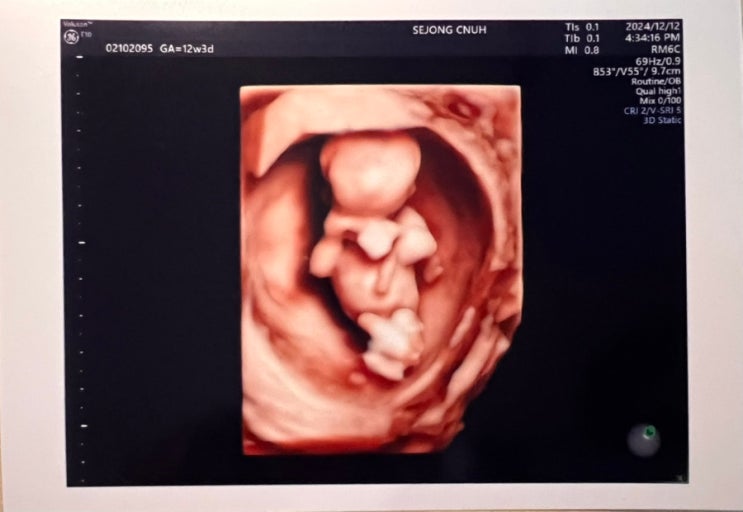

[12주 3일] 세종충대병원 1차 기형아검사

안녕하세요. 토디맘입니다:D 드디어 12주차입니다. 1차 기형아 검사를 하러 세종충대에 다녀왔어요. 4시 3...